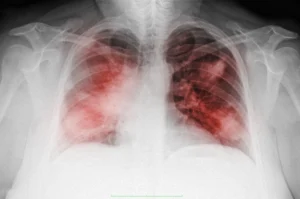

Пневмония: симптомы и лечение

Пневмония — это воспаление легких, вызванное инфекцией, которое может быть вызвано бактериями, вирусами или грибками. Это заболевание представляет собой серьезную угрозу для здоровья, особенно для детей, пожилых людей и людей с ослабленной иммунной системой. В данной статье мы рассмотрим основные симптомы пневмонии, методы диагностики и современные подходы к лечению. Что такое пневмония? Пневмония — это …